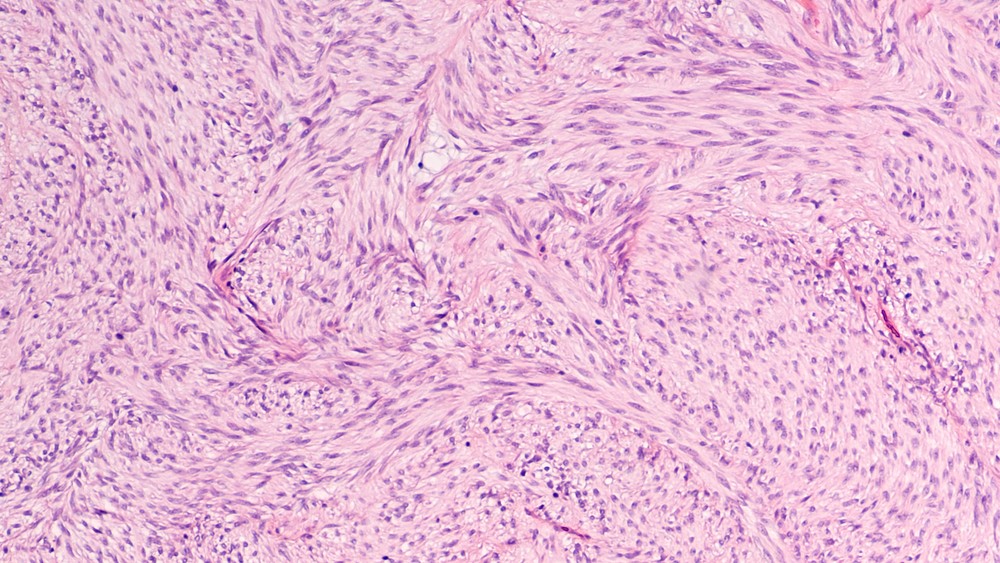

胃腸道基質瘤是什麼?

腸胃道基質瘤,常發生於50歲以上民眾,男女患病比例相當,一旦確診為腸胃道間質基癌,多半為惡性腫瘤。最常見於胃部,比例約佔50%;小腸佔25%;食道、直腸約15%;大腸佔10%,其中位於腸的基質瘤復發風險會相對較高。至目前,醫學界仍未不清楚基質細胞瘤的形成原因,但相信是由於基因變異所致。

此症徵狀與胃癌相似,大眾或會因而混淆,不過這兩種癌症的好發部位、診斷與治療方式都不相同。腸胃道間質基瘤主要是發生在腸胃道黏膜下層或肌肉層;胃癌則主要發生在胃黏膜細胞。而在治療方面,胃癌易發生淋巴轉移,大多需配合淋巴廓清術,且需配合化學治療;而腸胃道基質瘤主要治療則是進行手術切除及用標靶藥。